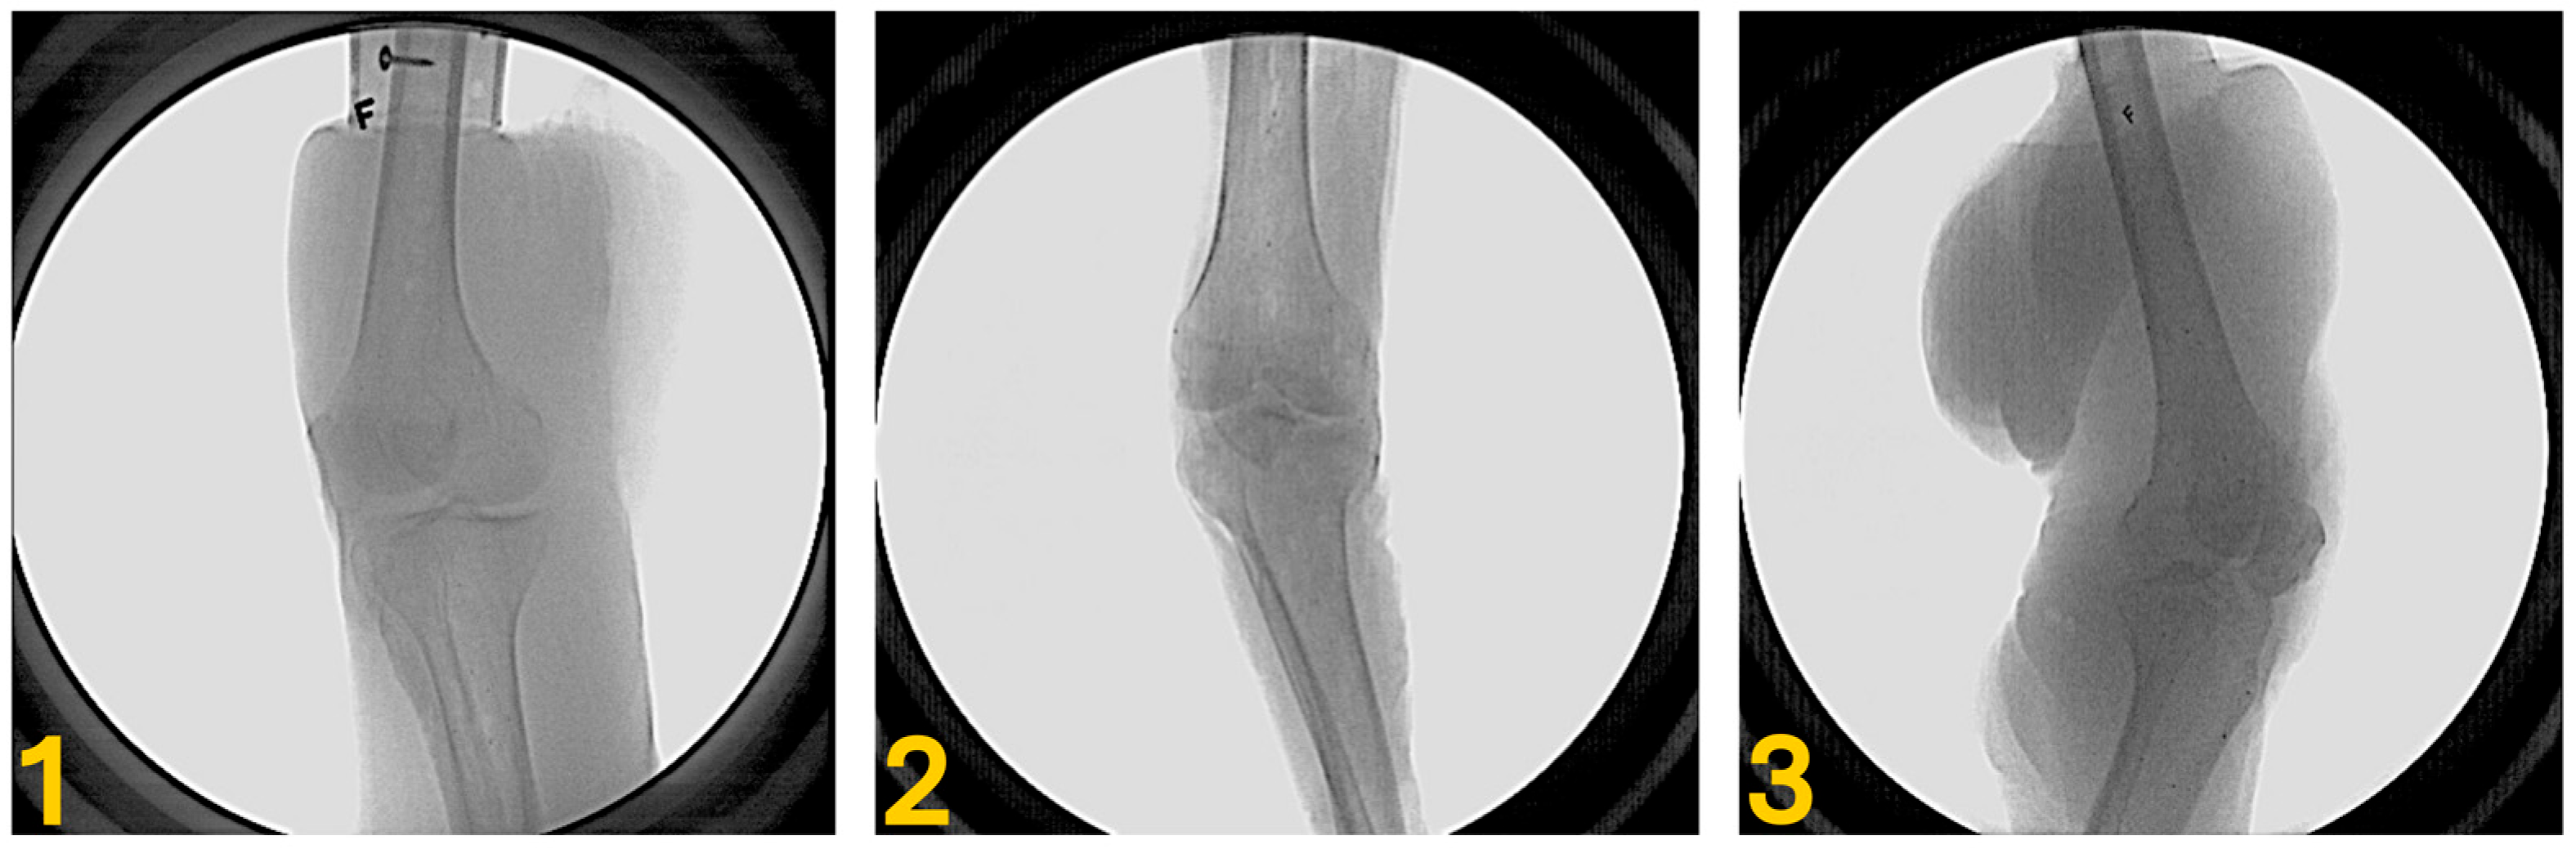

2.1. Specimen Preparation

2.2. Bone Model and Volume Generation